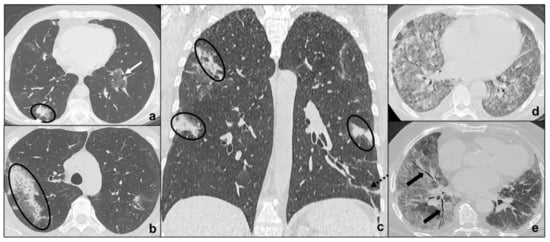

Idiopathic Pulmonary Fibrosis

Non-Specific Interstitial Pneumonia

Cryptogenic Organizing Pneumonia

Acute Interstitial Pneumonia